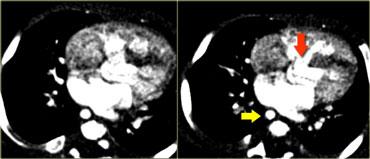

On the left a patient with a right arch with an aberrant left subclavian (indicated by the yellow arrow).

Scroll through the images on the left.

Again you have to realize that the axial CT-images have a ‘view from feet’.

Which vessels are indicated by the yellow and green arrow?

There is a right arch and the left subclavian artery is the last branch of the aortic arch, indicating that this is an aberrant left subclavian.

Medially to the left subclavian artery we see the left common carotid, that originates from the right side and has an oblique course to the left.

The yellow arrow indicates the azygos vein.

The green arrow indicates the left superior intercostal vein, a normal variant, that we will discuss later.

Same patient.

Posterior oblique view of volume rendered image to show the aberrant left subclavian artery.